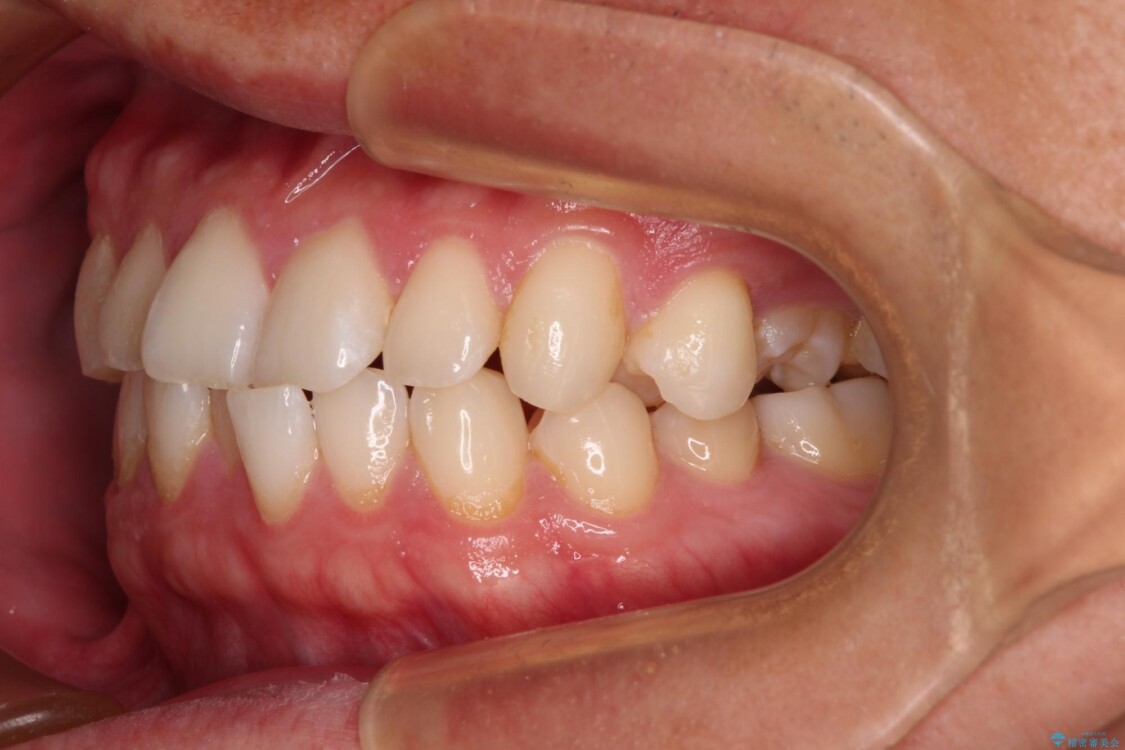

主訴:前歯のデコボコと奥歯のかみ合わせを治したい 今回ご紹介するのは、「前歯のガタガタ(叢生)」と「奥歯のかみ合わせ(シザーズバイト)」にお悩みでご来院された患者様の症例です。 患者様は、 ・歯並びをできるだけ早く改善したい ・費用を抑えた矯正治療 というご要望をお持ちでした。

・上顎左右の第二大臼歯が頬側へ転移し、シザーズバイト(scissors bite)の状態

・上顎左側第二小臼歯が90度捻転しており、噛み合わせに影響

治療前

• 前歯のガタガタ・奥歯のかみ合わせ(シザーズバイト)を改善|1年半で完了したメタルブラケット矯正 治療前画像